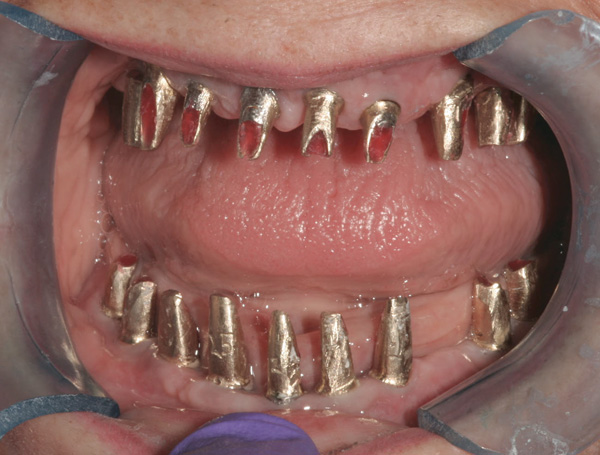

Background: This patient had a failing maxillary dentition and refused to wear a removable prosthesis. A staged approach was employed to retain some of his natural tooth abutments, and recession was noticed at the time of the impression for the second group of implants. Figure 1 shows the patient following insertion of the first set of implant custom abutments; the adjacent natural teeth are still present to support the provisional bridge. Seven months later, as shown in Figure 2, those first-stage custom abutments exhibited evidence of 1 mm to 3 mm of recession.

Results: A decision was made to re-prepare all of the abutments intraorally (Figure 3) so that all abutment margins would be at or below the gingival margin. (Of note, tooth Nos. 8 and 9, also shown in Figure 3, were later submerged for the case to be fully implant-supported.) While re-preparation greatly improved the esthetics of the final result, it required retraction cord placement, new impressions, and new castings.

(Note: A separate but similar type of case shown in Figure 4 and Figure 5 further illustrates intraoral abutment re-preparation.)

Figure 3 Abutments re-prepared intraorally.

Figure 3

Figure 4 Following osseointegration of an implant at No. 12, recession was observed at the fixture-level impression stage of No. 13; it was decided to re-prepare the margins of the CAD/CAM custom abutment of implant No. 12. Retraction cord was placed prior to preparation to avoid tissue injury and improve visibility of both tooth No. 11 and the implant custom abutment margin. As expected, recession was greater along the distal side of abutment No. 12, adjacent to the healed extraction/newer implant site.

Figure 4

Figure 5 Newly placed custom abutment on No. 13 with the previously re-prepared abutment at No. 12. No new recession has occurred since the case was completed more than 3 years ago.

Figure 5